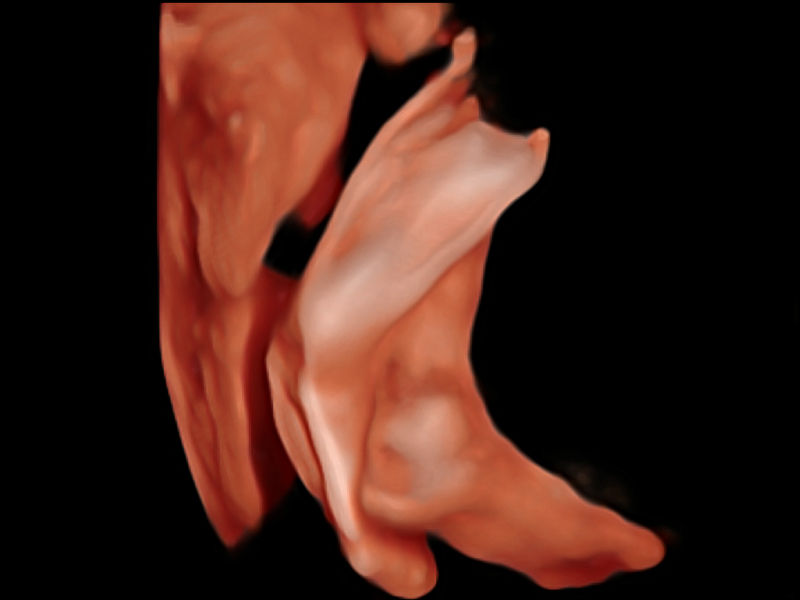

凸阵、线阵和相控阵探头进行实时扫描时,开启扩展成像模式,可以扩展超声图像视野,以便更完整地查看大的病灶或组织器官的解剖结构。